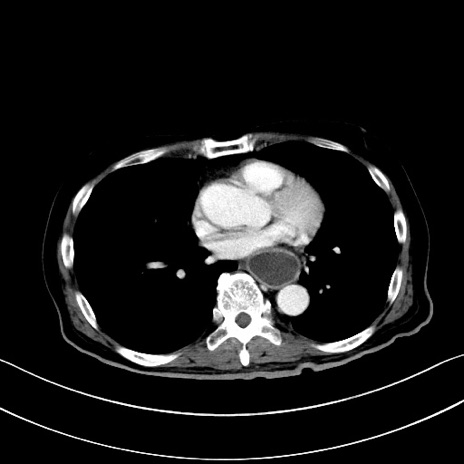

症例28(横断像)

【症例】60歳代男性

【主訴】嘔吐

【現病歴】胃癌にて胃全摘後。食思不振が悪化し、夜中に嘔吐することがある。

【既往歴】胃癌、胃全摘、脾摘、胆摘後

【データ】WBC 5900、CRP 10.56